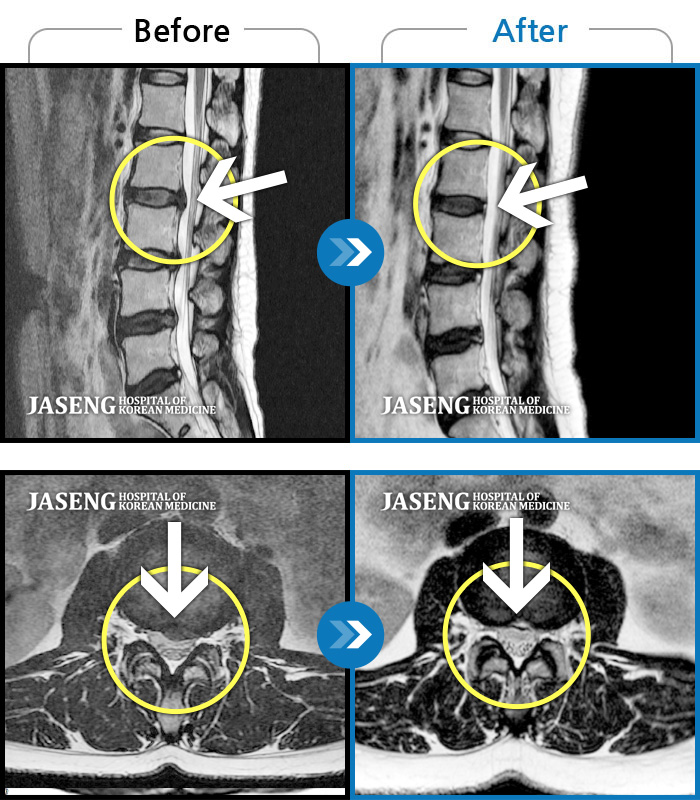

3년 전 허리가 너무 아파 병원에 갔더니 허리디스크라는 진단을 받았습니다.

하지만 일을 하느라 마땅히 쉴시간도 없고 여유를 가지고 치료할 시간도 없었습니다.

여러곳의 병원과 한의원도 댜녀 보았고 민간요법도 받아 보았지만 별소용이 없어 수술을 할까 고민하던 중, 창원에 자생병원이 개원한다는 소식을 듣고 반신반의 하면서 병원을 찾게되었습니다.

강만호 원장님을 만나게 되었고 2개월째 치료를 받고 있습니다. 허리와 다리에 통증이 심해 일상생활하기가 힘들고 고통스러웠는데 지금은 별 통증 없이 생활 할수 있게 되었습니다.